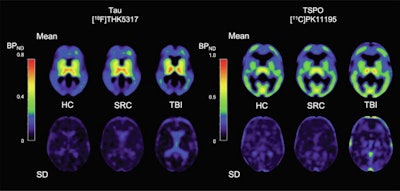

Image shows mean THK5317 and PK11195 nondisplaceable binding potential (BPND) for controls, rSRC and TBI patients, depicting tau and translocator protein (TSPO) expression, as well as corresponding standard deviation images. In symptomatic rSRC athletes, a voxel-wise t-test showed clusters of significantly increased THK5317 binding in the corpus callosum and subcortically including the medial temporal region and PK11195 binding in the medial temporal lobes. In TBI, elevated tau and TSPO binding was observed in the thalamus, temporal lobe white matter and midbrain. Significant group differences in total tau load were found between healthy controls and rSRC in subcortical grey matter (SRC 7.5 ± 0.9, controls 6.7 ± 0.5, p = 0.038), although not between TBI patients and controls. No significant differences in the number of voxels with THK5317 BPND > 0.5 or skewness in BPND distribution were found. Image courtesy of NeuroImage: Clinical.

In athletes with sports-related concussions, increased neuroinflammation was observed on PET in medial temporal lobes, and tau aggregation was observed in the corpus callosum. In TBI patients, widespread white matter tau aggregation and neuroinflammation were found.